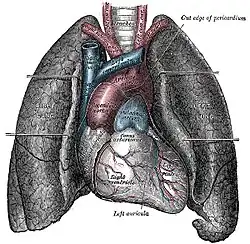

Morphologie

Dans le corps humain, le cœur se situe dans la région thoracique (poitrine), où il occupe plus précisément la portion antéro-inférieure du médiastin entre la seconde et le cinquième espace intercostale. Il est situé sur la ligne médiane, un peu décalé à gauche de telle sorte que deux tiers de sa masse sont situés du côté gauche. C'est la position dite de lévocardie, qui est normale sauf en cas de malformation congénitale ayant inversé la position des autres organes entre la gauche et la droite (situs inversus). D'autres malformations de naissance peuvent placer le cœur à droite (dextrocardie) ou au milieu (mésocardie (pt))[1]. Le cœur est contenu dans la cavité péricardique qu'il occupe entièrement, et il est entouré par les poumons (recouverts de la plèvre) de chaque côté, le diaphragme en bas, le sternum en avant, l'œsophage en arrière et les troncs artériels (aorte et artère pulmonaire) en haut.

Face sterno-costale du cœur

La face sterno-costale (ou face antérieure) du cœur est dirigée en avant, en haut et légèrement sur la gauche.

Elle est marquée par le sillon interventriculaire antérieur qui sépare les faces antérieures des ventricules droit et gauche et par le sillon coronaire qui sépare les atriums en arrière des ventricules en avant.

Les deux tiers de la face antérieure est constituée de la paroi antérieure du ventricule droit.

Au niveau de la partie moyenne du sillon coronaire, émergent l'aorte et le tronc pulmonaire.

Elle est séparée du sternum et des côtes par le péricarde.

Elle est limitée à droite par le bord droit du cœur qui la sépare de la face diaphragmatique.

Elle est limitée à gauche par le bord gauche du cœur qui est convexe latéralement et qui la sépare de la face pulmonaire gauche.

Face pulmonaire droite du cœur

La face pulmonaire droite du cœur est formée par la paroi de l'atrium droit entre en haut la veine cave supérieure et en bas la veine cave inférieure.

Elle est légèrement convexe vers la droite et elle est séparée de la face médiastinale du poumon droit par la plèvre et le péricarde.

Face pulmonaire gauche du cœur

La face pulmonaire gauche du cœur est formée par la paroi du ventricule gauche. Elle est située dans l'empreinte cardiaque située sur la face médiastinale du poumon gauche. Elle en est séparée par la plèvre et le péricarde.